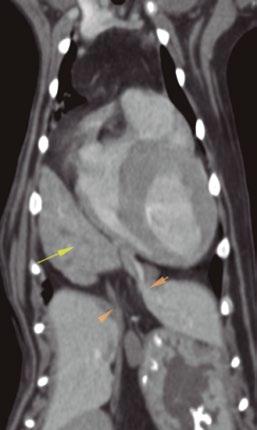

Utilidad clínica de la ecografía pulmonar y cardiaca en urgencias